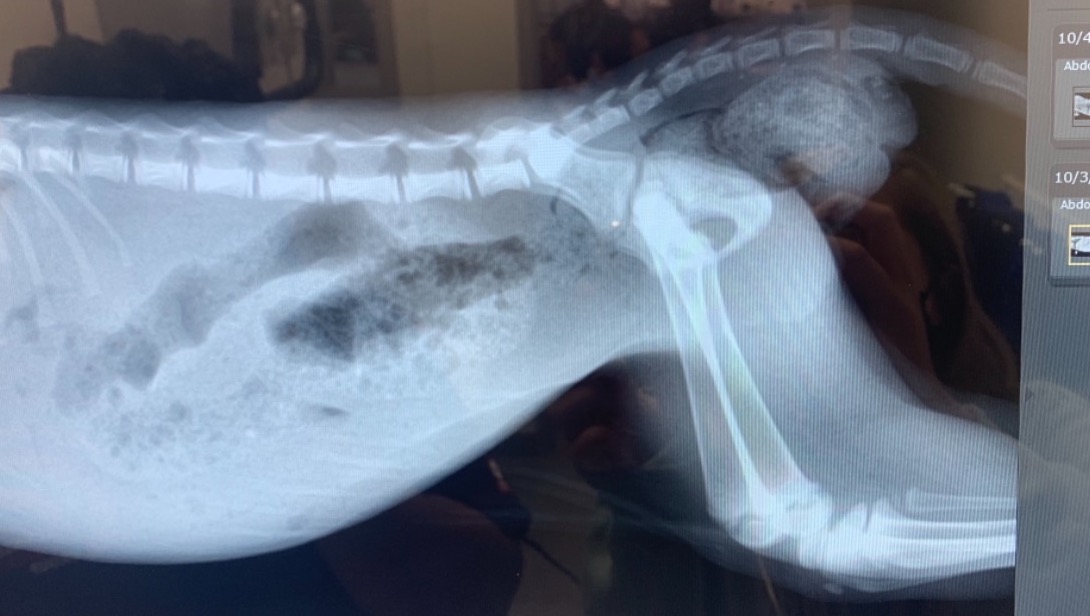

But then I got constipated! And that’s been the latest struggle of me, Maple, the itty bitty shitty kitty. Since then I’ve struggled to poop, have had several enemas, IV’s, overnight stays and X-rays to find out what’s wrong. They don’t know why, and are worried it may be a congenital issue that I may need surgery on. But because of my size and age my options aren’t great.